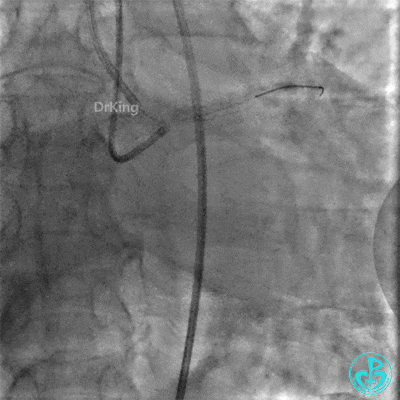

EBU指引导管左冠脉造影显示粗大前降支中段闭塞,闭塞段近端有对角支发出,前降支同侧逆向显影,闭塞段不长。